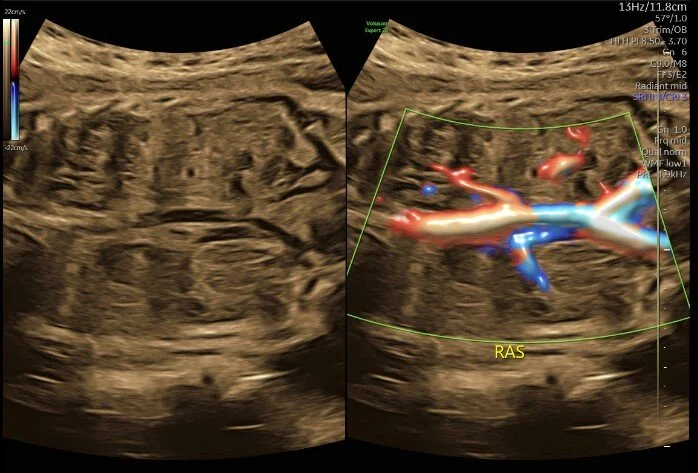

Patient was referred to MFM office for intrauterine growth restriction and incomplete anatomy views from her primary OB office. Upon ultrasound examination, an absent left kidney was quickly suspected, then later located superior to the stomach. Two weeks later, the patient returned for an amniocentesis and Dopplers.

Patient was sent for an MRI due to a possible ectopic kidney or congenital diaphragmatic hernia based on ultrasound exam. The MRI confirmed a posterior congenital diaphragmatic hernia containing the left kidney, adrenal, and bowel.